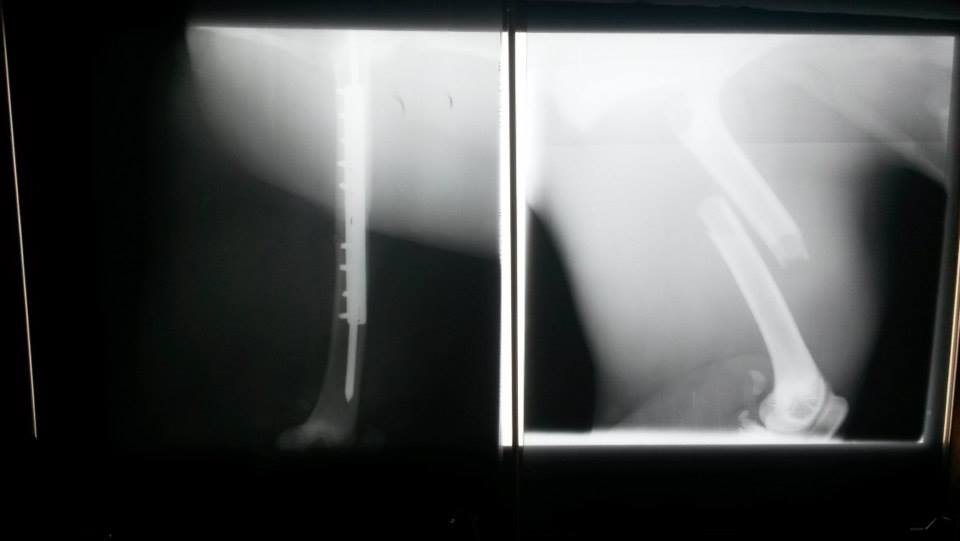

We use our X-ray equipment almost every day as a part of our periodical health check protocols and of course as a diagnostic tool for a wide variety of clinical cases. We deal with wild species that are very prone to suffer from stress and may create dangerous situations. For these reasons we need versatile and reliable X-ray equipment that we can use in the surgery room and in the field. Recently one of our Cheetah joungsters broke her femur and our GIERTH HF 100 plus was an invaluable tool for diagnsotic and prognostic of the fracture.